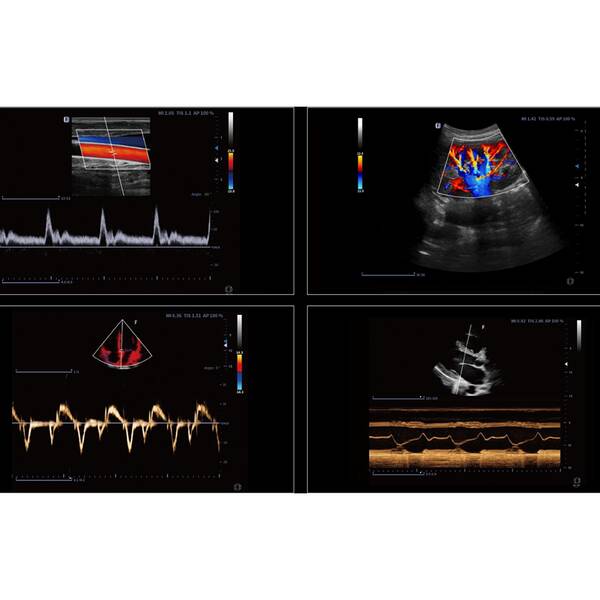

- Hi Platform — представляє абсолютно нову модернізовану платформу "HI" з інтелектуальним двоядерним процесором, що забезпечує надійну потужність паралельної обробки променів. Зображення з повним фокусуванням покращує чіткість кожної ділянки та забезпечує стабільну високу роздільну здатність. Технологія фазової візуалізації кровотоку використовує інформацію про час і просторові параметри для поліпшення захоплення сигналів низькошвидкісного кровотоку і рухомих тканин, ефективно пригнічує перешкоди сигналу, не пов'язаного з кровотоком.

- SNS+ — автоматичне виявлення і придушення спекл-шумів за допомогою багатовимірного алгоритму, що забезпечує отримання і поліпшення деталізації зображення при дослідженнях у різних напрямках. Миттєве отримання зображення меж великих органів і пошкоджених ділянок на субміліметровому рівні.